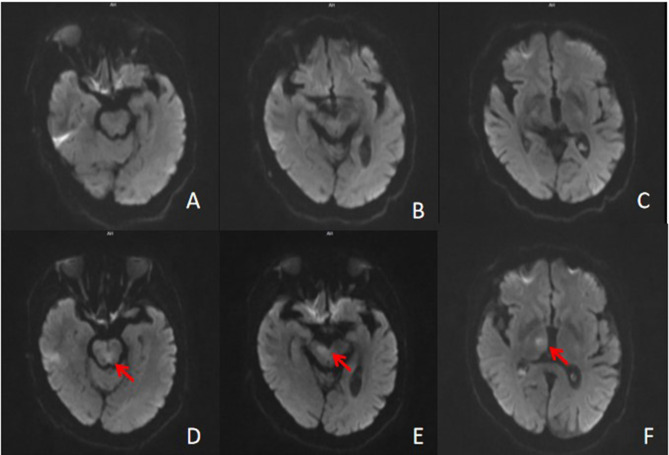

急性椎基底动脉闭塞(AVBAO)仅占缺血性卒中的1-2%,但致残率和死亡率高。机械取栓联合静脉溶栓可快速实现血管再通,显著改善患者预后。本报告描述一名73岁男性因AVBAO昏迷入院。MT后,基底动脉再通成功;然而,患者随后发展为罕见但严重的双侧动眼神经麻痹并发症。该报告强调需要仔细的术前计划,包括血管解剖和血栓特征的详细评估,以及操作人员专业知识的重要性。改进术中技术和密切的术后监测可能有助于预防并发症,如血管损伤或栓塞复发。此外,临床医生应该意识到早期DWI(弥散加权成像)在检测脑干梗死方面的局限性,以及术后临床警惕的必要性。

Acute vertebrobasilar artery occlusion (AVBAO) accounts for only 1-2% of ischemic stroke, but it has high disability and mortality rates. Mechanical thrombectomy (MT) combined with intravenous thrombolysis can quickly achieve vascular recanalization and significantly improve patient prognosis. This report describes a 73-year-old male who was admitted to the hospital in a coma due to AVBAO. After MT, successful recanalization of the basilar artery was achieved; however, the patient subsequently developed the rare but serious complication of bilateral oculomotor nerve palsy. The report emphasizes the need for careful preoperative planning, including detailed assessment of vascular anatomy and thrombus characteristics, and the importance of operator expertise. Improved intraoperative technique and close postoperative monitoring may help prevent complications such as vessel injury or embolic recurrence. Additionally, clinicians should be aware of the limitations of early DWI (Diffusion-weighted imaging) in detecting brainstem infarcts and of the need for clinical vigilance in the postoperative period.